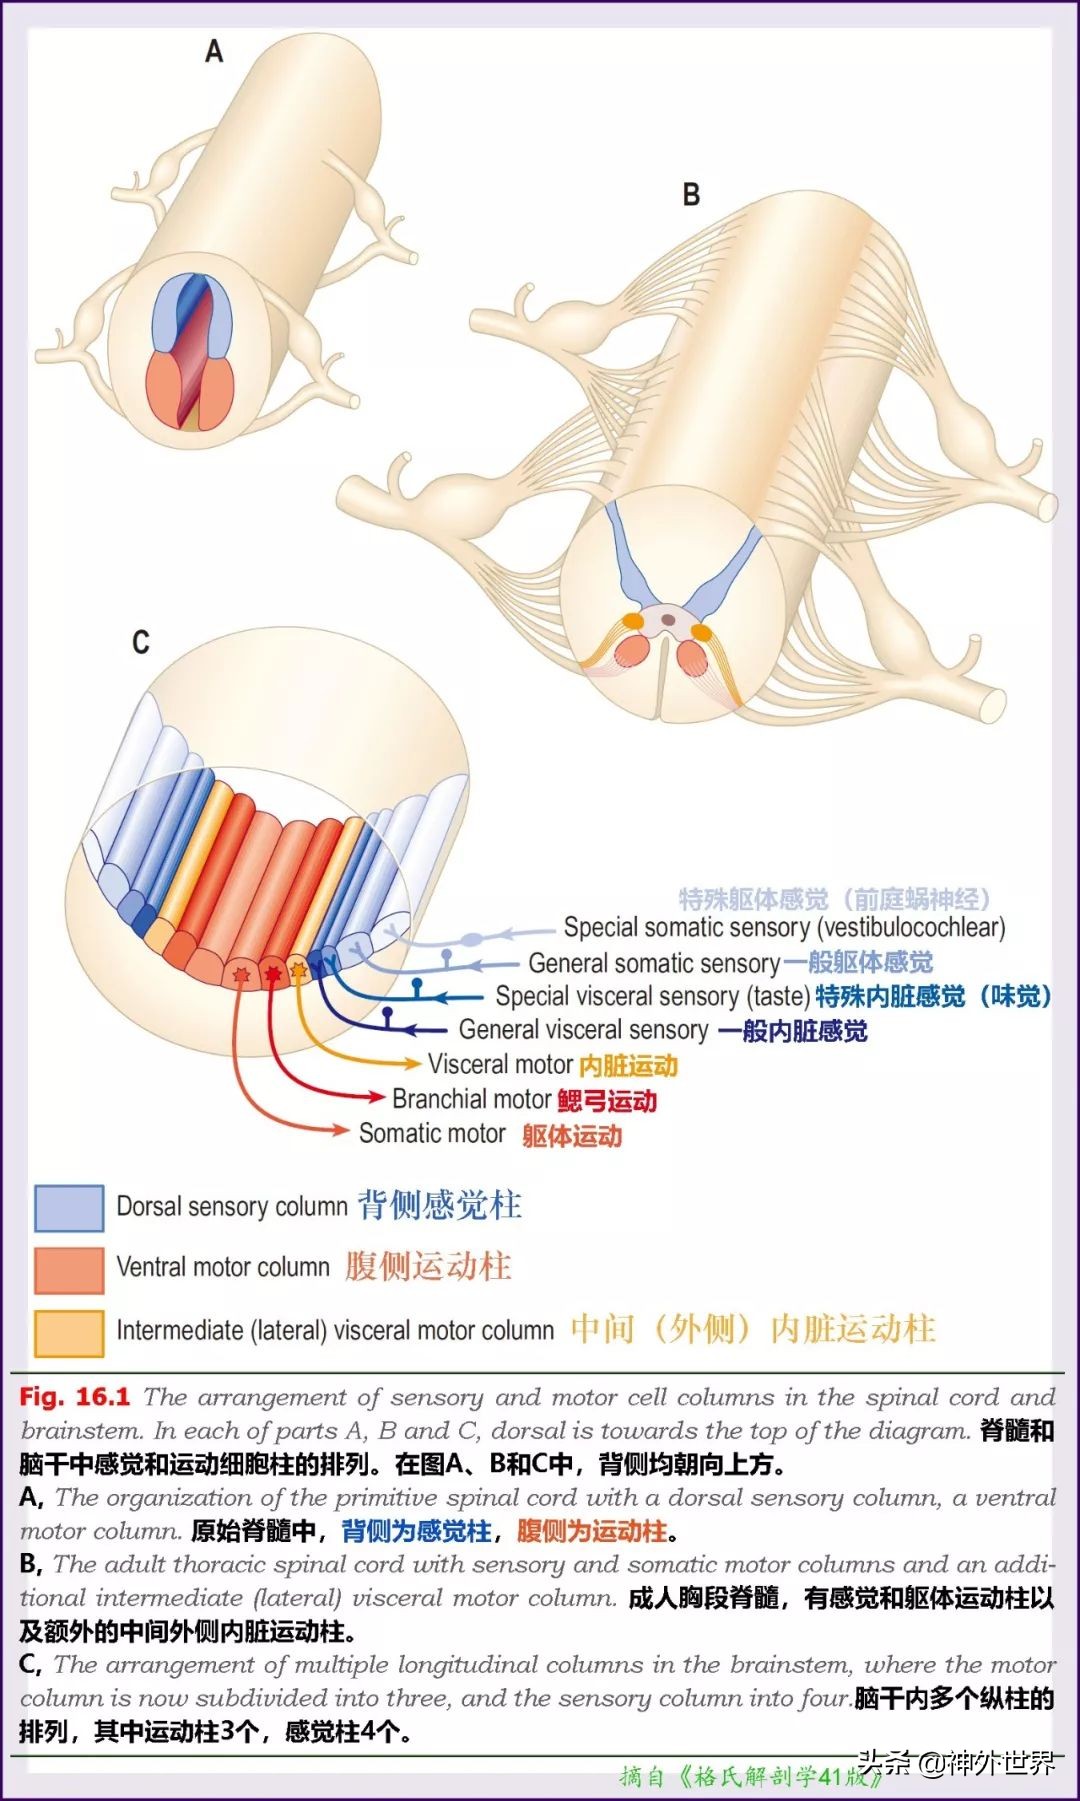

- 颅神经核与颅神经:①一核一功能,一神经一区域。②与脑干连接的10对颅神经中:动眼、滑车、外展神经支配眼球活动;迷走神经迷走至躯干的内脏支配内脏活动;舌咽、迷走、舌下与吞咽功能相关→后组颅神经麻痹致吞咽困难。③胚胎早期功能类别相同的颅神经核集中在一起形成个细胞功能柱,功能有7类,但功能柱只有6个(因为特殊内脏感觉和一般内脏感觉同在孤束核)。以后功能柱断裂成18个颅神经核。但神经核的排布还是按7个细胞功能柱的规律排列的(界沟以内为运动,界沟以外为感觉,具体排布规律看下图)。